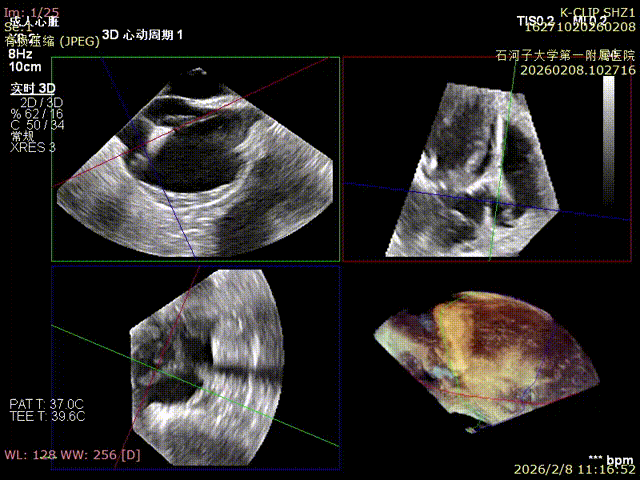

Comparison of preoperative reflux and postoperative reflux

Preoperative

Preoperative reflux

Postoperative

Postoperative reflux

Immediate Postoperative Echocardiographic Assessment: Tricuspid regurgitation was reduced from preoperative grade 4+ to grade 1+, the annulus diameter was reduced to 6.15 cm², and the leaflet coaptation was satisfactory.

Preoperative annulus area: 11.5 cm²

Postoperative annulus area: 6.15 cm²